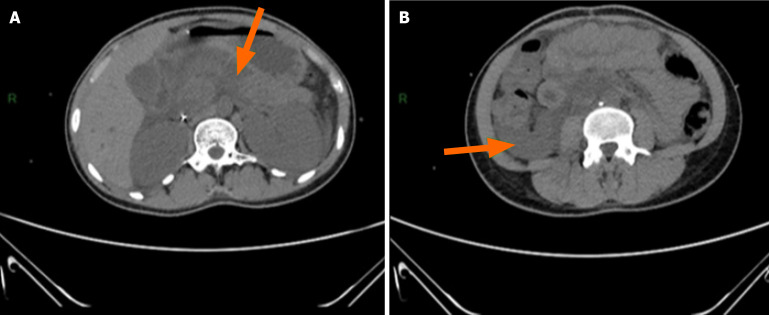

Case summary: A 20-year-old female was admitted to the emergency room for abdominal pelvic pain, fever, asthenia, polyuria, and polydipsia with a progressive deterioration of her state of consciousness. At admission, she was in a mild coma (Glasgow score: 9), had a fever of 38.5 °C, and had hyperglycemia (6 g/dL). The tests revealed severe DKA, hypertriglyceridemia, hyperamylasemia, and hyperlipasemia as well as malaria parasite density. The computed tomography scan confirmed acute stage E pancreatitis. The diagnosis was that of inaugural ketoacidosis of type 1 diabetes unbalanced by pancreatitis and malaria. Treatment included insulin therapy, rehydration, and antimalarial and analgesic treatment. After 10 days, the outcome was favorable with a normalization of the blood sugar, and an endocrine follow-up was recommend.